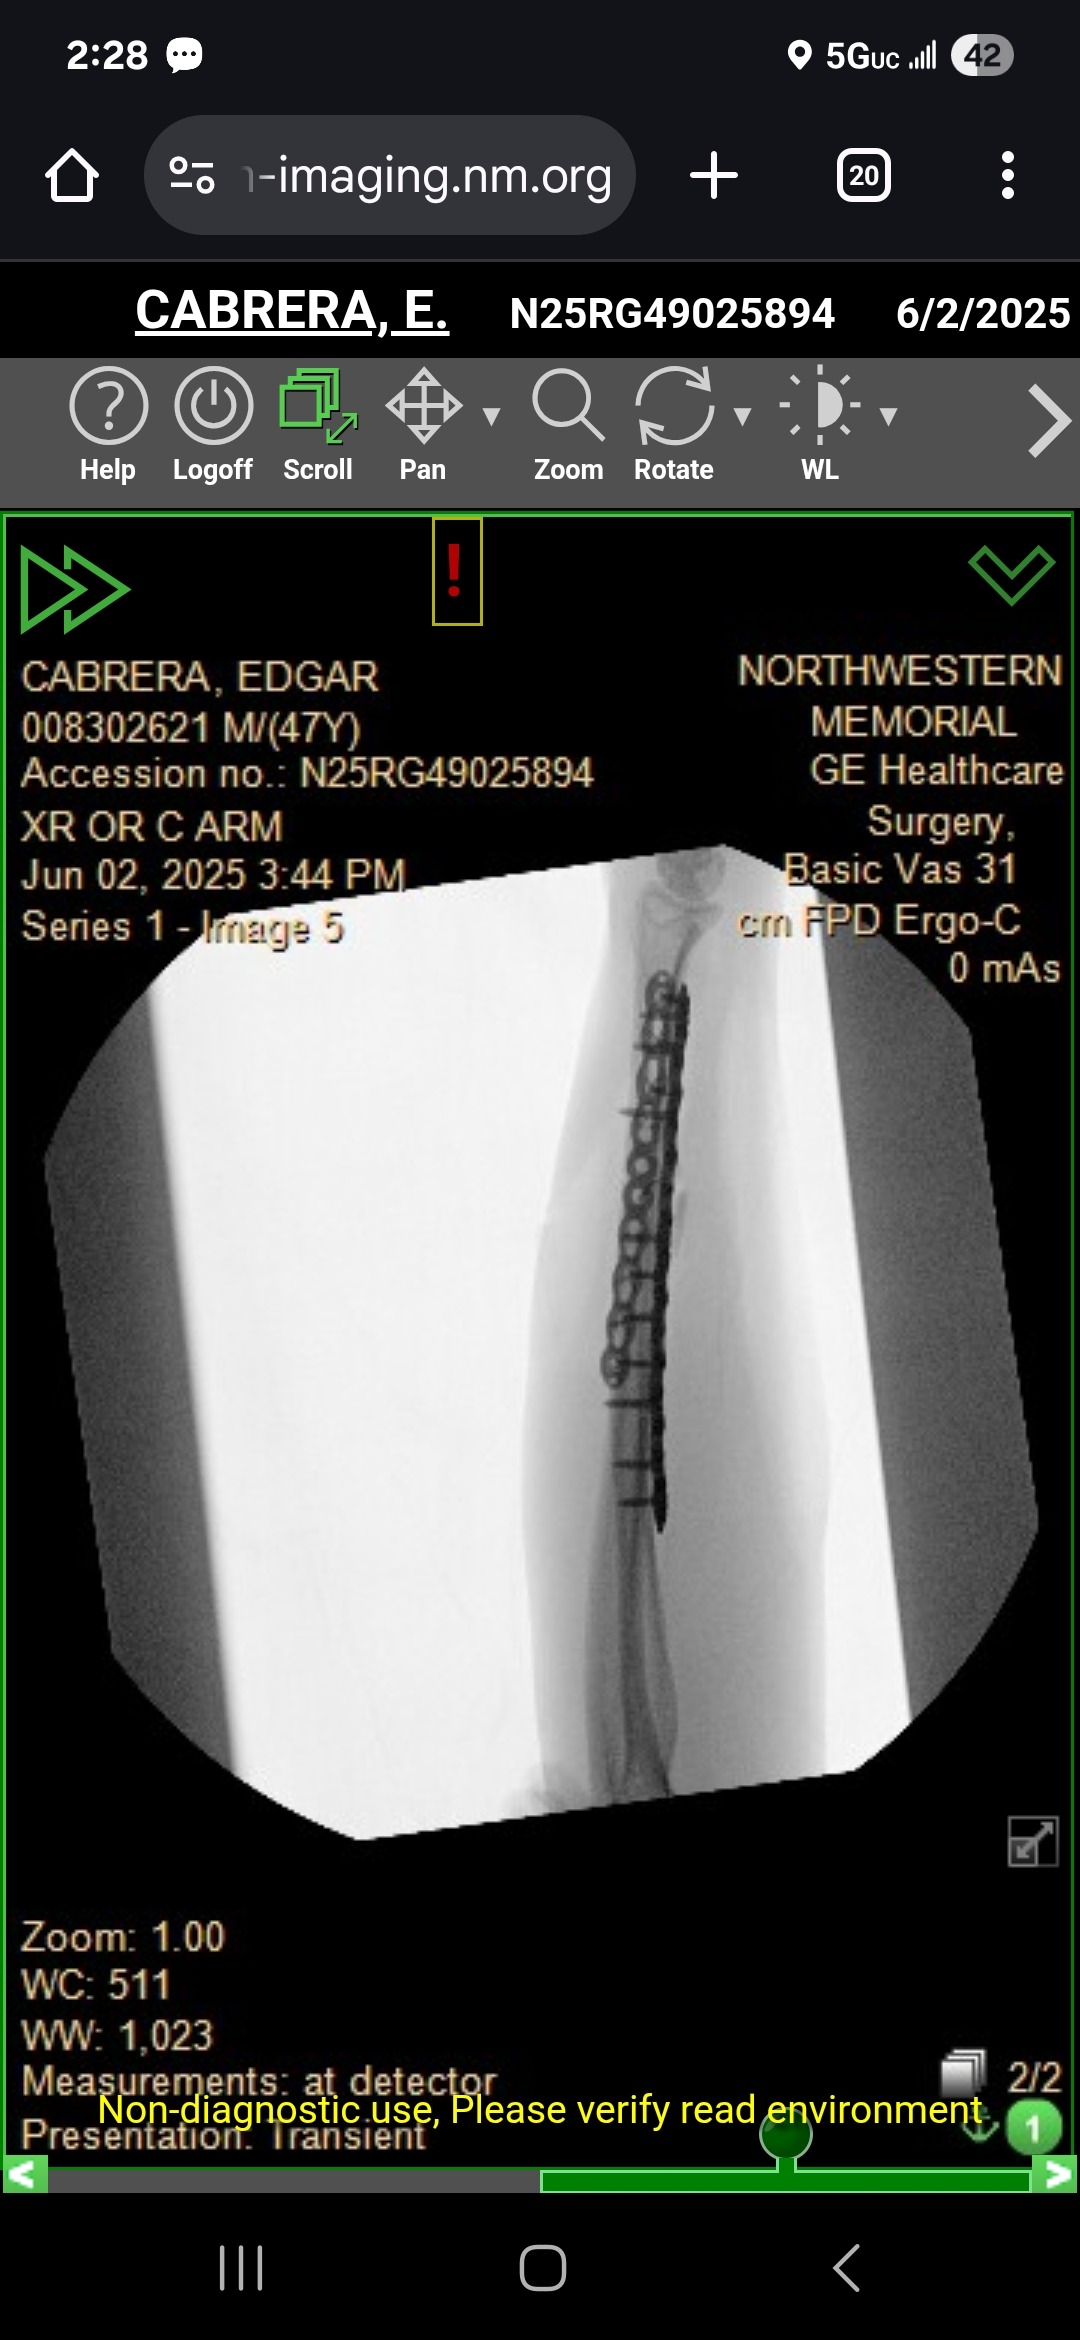

Hello everyone, my name is Ed Cabrera, and I was involved in a bike accident on June 1, 2025. I ended up with a broken arm that went clean through my skin and needed surgery, for which they put steel plates and screws in my arm.